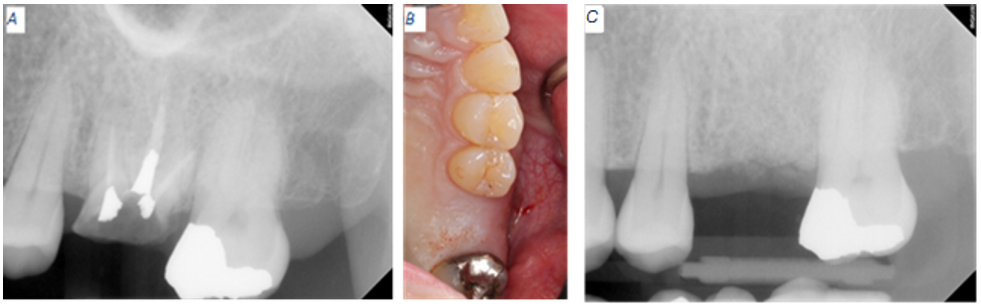

Concerning the mandibular left side, tooth #18 presented with recurrent caries around a composite restoration that replaced the distolingual cusp. The distal margin of this composite projects apically beyond the cavity preparation and appeared to approach the crestal bone (Fig 2).

Figure 2: Baseline radiographic and clinical appearance for tooth #18. (A) Excess restorative material nearing the alveolar bone. (B) Recurrent caries around the composite restoration.